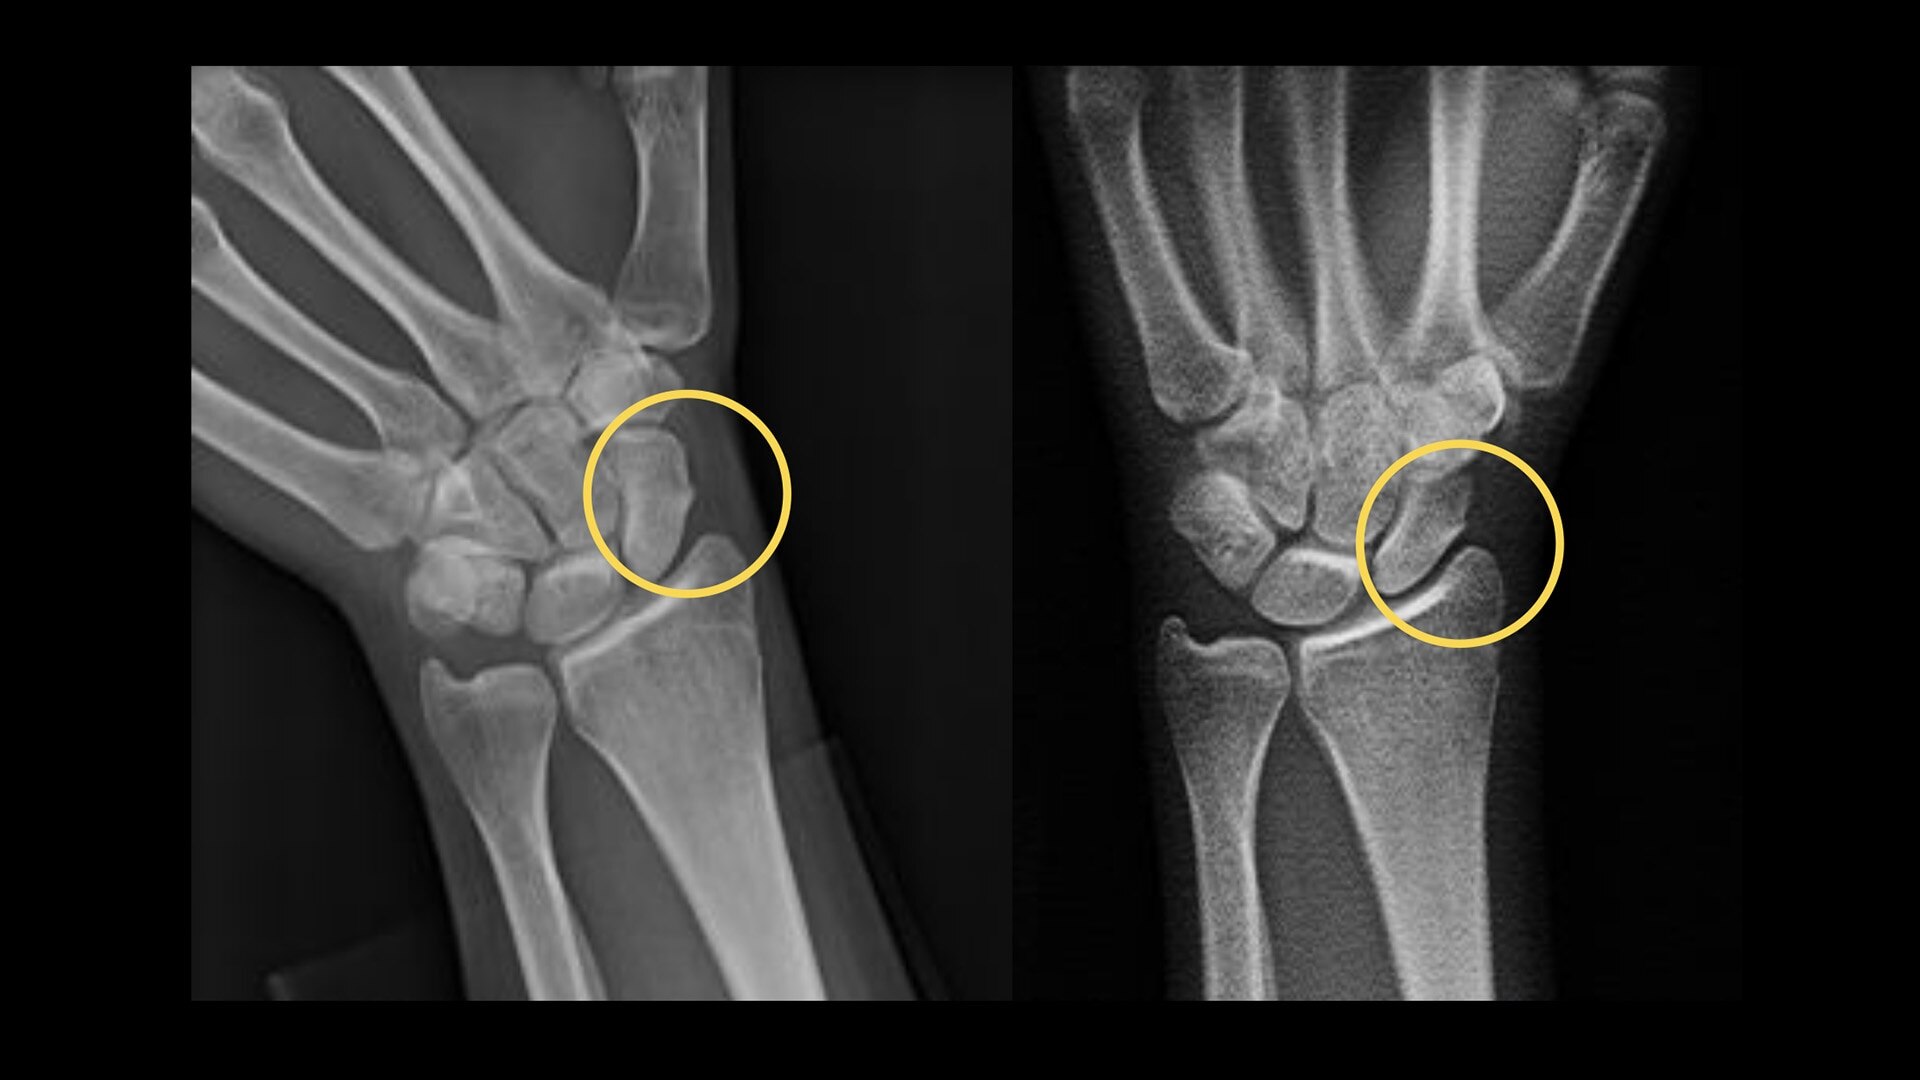

80%

Sensitivity in the detection of scaphoid fractures on average6,7

Your department relies on standard radiography as the first diagnostic test for most chest, orthopedic and trauma cases. But hairline fractures or non-displaced fractures are difficult to detect on conventional X-rays.13 According to a recent study, 33% of scaphoid fractures are missed on the first X-ray.14

14. Geijer M et al. "Clinical utility of tomosynthesis in suspected scaphoid fracture: A pilot study" Skeletal Radiol. (Jul 2011): 40(7):863-7.